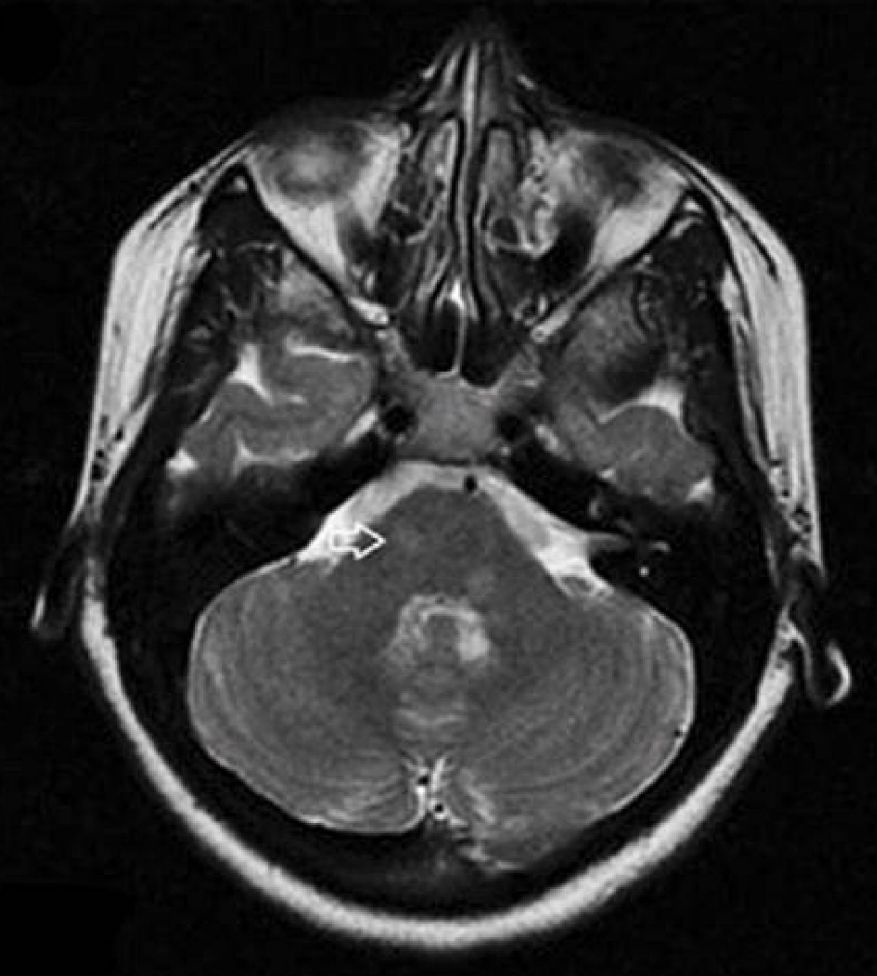

男性,50岁。“吞咽困难、右侧肢体无力4天”入院。查体:右侧Horner征+, 咽反射消失。右侧共济运动不稳。

答案:特殊类型延髓梗死——Opalski综合征。

Opalski综合征的临床表现为延髓背外侧综合征(即Wallenberg综合征)伴有同侧肢体轻偏瘫,曾被认为是延髓背外侧综合征的变异。定位于延髓背外侧中下部。MR影像上除延髓背外侧表现为DWI高信号外,肢体轻瘫同侧的小脑后下动脉和(或)椎动脉闭塞较具特征性。本病例旨在提醒大家,若患者出现显著吞咽困难伴有偏瘫时,不要忘了病灶可能在偏瘫同侧,这对选择性动脉溶栓很有指导意义。